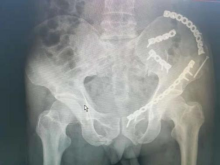

5.复杂骨盆骨折

6.髋臼骨折